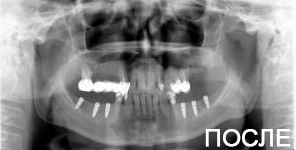

4 работы в портфолио

Удаления зубов любой сложности. Пародонтология (закрытый, открытый кюретаж, лоскутные операции, рецекция верхушки корня, вестибулопластика, френулотомия, френулоэктомия). Переостотомия, вскрытие абсцессов и других воспалительных процессов. Цистотомия, цистэктомия. Имплантология (установка имплантатов различных систем с осложненными анатомическими условиями, направленная костная регенерация, открытый синус-лифтинг, закрытый синус-лифтинг, пластика альвеолярного гребня).

Акопян Антон Владимирович: портфолио (4)